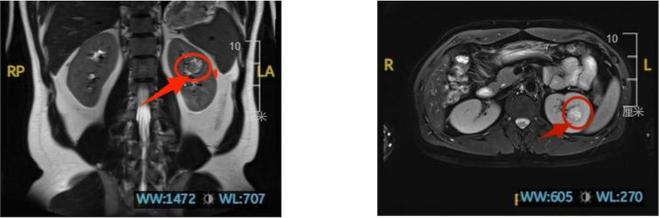

幸福的生活轨迹,在郑先生成为双胞胎父亲不久后戛然而生。2024年,单位体检的腹部B超报告上,“左肾占位”四个字像一块巨石压在他心头。“当时还心存侥幸,觉得可能只是普通囊肿。”郑先生回忆,直到一个月后,医院的CT结果击碎了他的幻想——左肾内生型恶性肿瘤,且肿瘤藏在肾脏中央,而非附着于表面。

“这种肿瘤像埋在肾脏里的‘定时炸弹’,位置太深,手术时看不见摸不着,稍不注意就可能要切整个肾。”接诊医生的话让他如坠冰窟。因肿瘤位置特殊,当地医生建议他们前往北京、上海等地求医。怀揣最后希望的郑先生辗转至上海,然而,即便是国内顶尖医院的专家,也无法承诺“保肾”。“上海的医生说风险太高,不敢保证能保住肾脏。”郑先生回忆,当时他看着两个年幼的孩子,想到可能要失去一个肾脏,几乎绝望。

王科主任团队面临的挑战堪称“极限考验”:肿瘤位于肾脏中央,表面无法直接观察,手术时需先阻断肾动脉,且必须在30分钟内完成肿瘤切除与肾脏缝合——超过这个时间,肾脏就可能因缺血失去功能。“就像在‘盲盒’里找肿瘤,还得在‘倒计时’内精准切除、完美缝合,一步错就可能导致手术失败,甚至危及生命。”王科主任形象地比喻。

关键时刻,3D腹腔镜技术成为“利器”。与传统平面腹腔镜不同,3D技术能呈现立体解剖结构,让手术视野中的血管、组织层次清晰可辨。“就像从看2D电影变成3D实景,血管走向、肿瘤边界一目了然,操作准确度和把握度大幅提升。”王科主任解释,借助这项技术,团队在短短半小时内精准找到肿瘤、完整切除,并细致缝合肾脏,成功完成保肾手术。